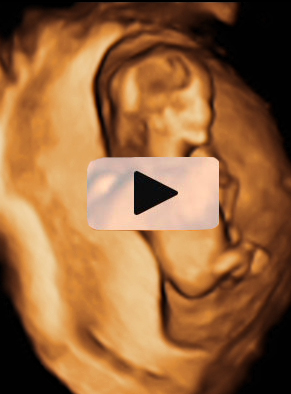

Ecografía semana 12: Bebé hacidendo movimientos vigorosos

He aquí un signo inequívoco de bienestar fetal: los movimientos vigorosos de un bebé en su semana 12 de gestación. La ecografía 4D muestra al niño en movimiento, junto con la placenta y el cordón umbilical dentro de la cavidad uterina.

Ecografía en 4D de feto de 12 semanas en movimiento

La variedad de movimientos de este bebé de 12 semanas de gestación es muy amplia. Las imágenes muestran cómo cambia de postura varias veces y agita con energía brazos y piernas. Para los ginecólogos, los movimientos de la criatura indican vitalidad, son un signo positivo de salud fetal. En la ecografía en 4D (vídeo) se aprecian casi todas las estructuras externas de la criatura, además del cordón umbilical y la placenta (ambos conectados entre sí), en el margen superior izquierdo de la cavidad uterina.